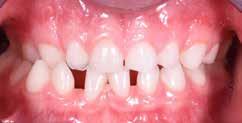

Presentazione del caso > F.V, bambino di cinque anni, presenta una malocclusione di II Classe scheletrica, III Classe dentale molare e canina destra e sinistra, morso inverso anteriore. Le arcate dentali mostrano usura degli elementi dentari anteriori a causa dell’occlusione patologica. Le linee mediane, superiore ed inferiore, sono centrate; il frenulo labiale superiore patologico per un’eccessiva estensione inter-incisale.

Il piano di trattamento prevede l’utilizzo di un dispositivo elastodontico di III Classe, da portare per due ore diurne e tutte le notti in modo passivo, senza effettuare alcun esercizio, al fine di ripristinare una relazione molare e canina bilaterale di I Classe ed il corretto avanzamento maxillare e inibire l’eccessiva crescita mandibolare. È possibile ottenere il risultato in pochissimi mesi di terapia, essendo la crescita del paziente molto attiva.

In un secondo momento, alla risoluzione della problematica scheletrica, si monitorizzerà il caso con visite semestrali in modo da reintervenire qualora si dovesse ripresentare la problematica.

Dall’esame clinico si evince la III Classe dentale, l’inversione anteriore e l’over-jet negativo.

Una volta ottenuta la correzione del rapporto molare ed incisale, l’apparecchio elastodontico verrà portato dal paziente solo durante la notte per stabilizzare il risultato ottenuto e guidare l’eruzione degli elementi dentari per un totale di quattordici mesi di terapia. ad inizio trattamento :

Considerazioni > L’analisi cefalometrica ad inizio trattamento dimostra la II Classe scheletrica con protrusione del mascellare superiore e prognazia mandibolare; tendenza alla crescita verticale. L’esame clinico evidenzia una protrusione mandibolare funzionale.